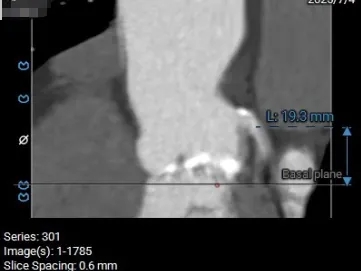

术前CT分析

主动脉根部测量

Annulus 20.7mm

LVOT 21.3mm

钙化积分 612

SOV

27.9*26.8*27.1mm

STJ 22.6mm

AAO 28.8mm

瓣上结构测量

瓣上2mm

20.5mm

瓣上4mm

19.9mm

瓣上6mm

20.7mm

瓣上8mm

20.2mm

瓣上10mm

20.8mm

瓣上12mm

21.9mm